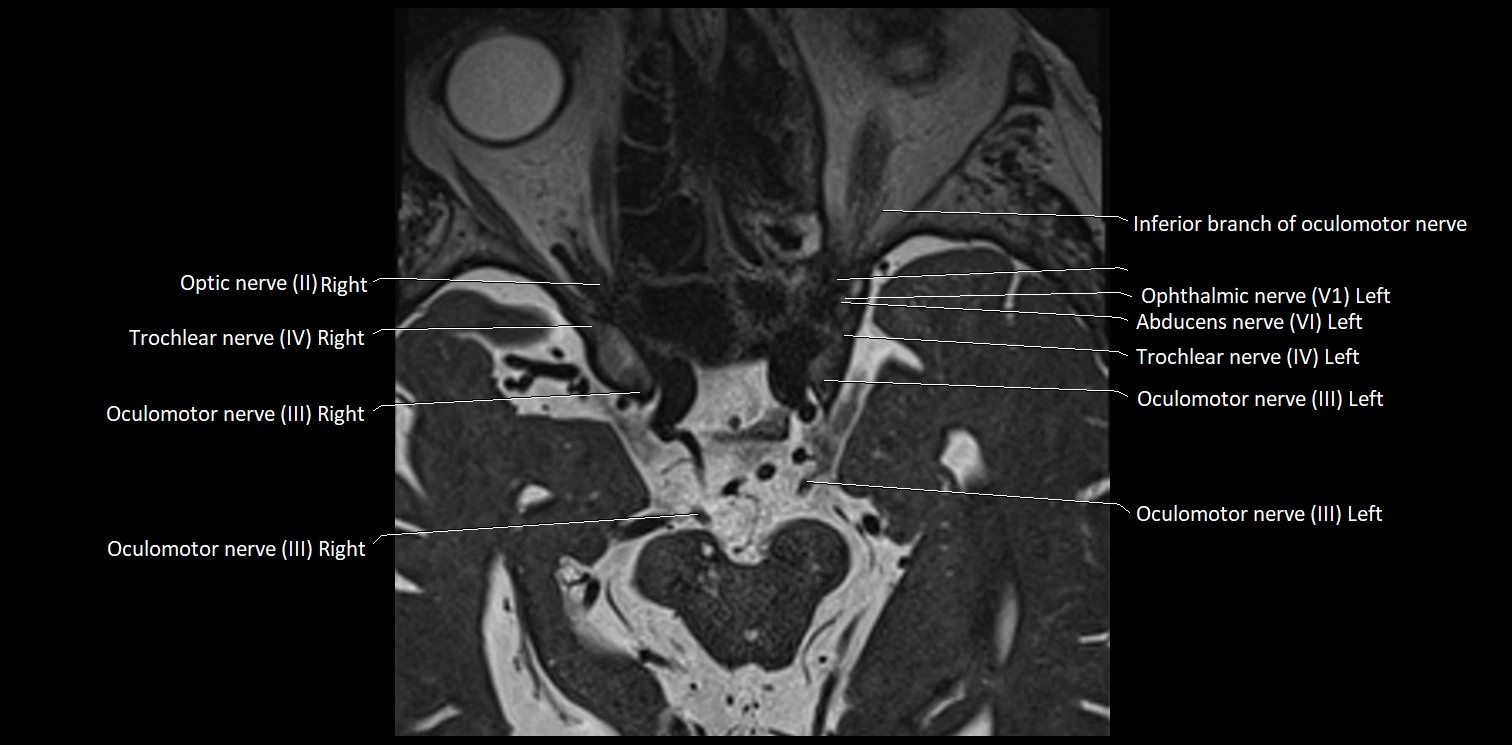

MRI Appearance

• The abducens nerve is a small, thin, linear structure

• Best visualized on high-resolution T2-weighted 3D MRI sequences (e.g., FIESTA or CISS)

• Seen as a hypointense (dark) line running from the brainstem at the pontomedullary junction, traversing the prepontine cistern, and entering Dorello’s canal under the petrosphenoidal ligament, then into the cavernous sinus, and finally the orbit

• May be challenging to visualize in standard MRI due to its small size

• Pathology may be inferred by absence, displacement, or enhancement of the nerve

MRI images

image